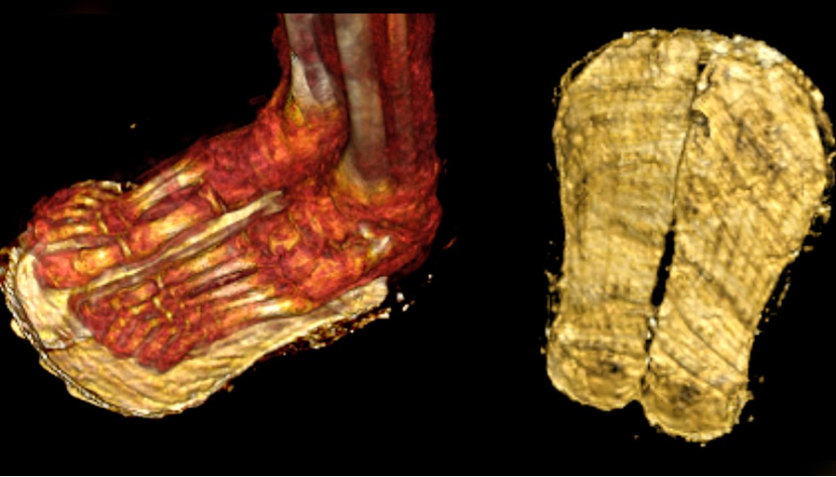

Sandálias brancas foram colocadas nos pés do garoto. O corpo foi também envolto em samambaias.

“As sandálias provavelmente foram usadas para permitir que o menino saísse do caixão. De acordo com ‘O Livro dos Mortos do Antigo Egito’, o falecido tinha de usar sandálias brancas para estar limpo e piedoso antes de recitar seus versos", explicou Saleem.